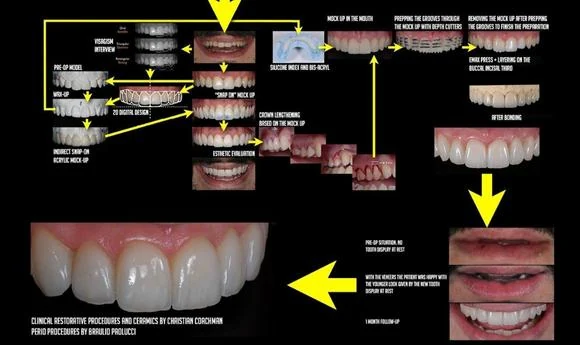

Before undergoing a Hollywood Smile procedure, patients will have a consultation with a cosmetic dentist. During this consultation, the dentist will assess the patient’s oral health, discuss the desired smile outcome, and recommend the most suitable treatment plan. X-rays, dental impressions, and photographs may be taken to aid in the treatment planning process.

The specific procedures involved in a Hollywood Smile vary depending on the individual treatment plan. Generally, the operation may include teeth whitening to achieve a bright base color, dental contouring to reshape and align the teeth, and the placement of veneers or other dental restorations. The dentist will ensure patient comfort throughout the process, and local anesthesia may be administered if necessary.